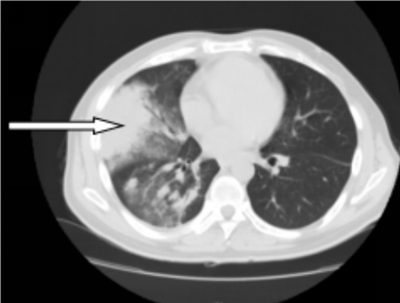

41岁的彭先生,2022年3月份出现咳嗽咳痰,多家医院治疗效果不佳,外院查胸部CT提示肺部占位及大量胸水,且外周血白细胞明显升高及颈部多发的淋巴结肿大。4月初疑诊结核收入香港马会app结核科,入院后发现浅表淋巴结进行性增大,经血液科会诊,考虑淋巴瘤并骨髓侵犯。患者转入血液内科后,行骨髓涂片提示有77%肿瘤细胞,同时请耳鼻喉科行颈部淋巴结切除病检,最终确诊为低级别滤泡性淋巴瘤并肺部、骨髓侵犯(IV期,EZH2基因突变阴性)。4月27日根据最新的滤泡性淋巴瘤诊治指南(NCCN指南及CSCO指南),选用GB方案(奥妥珠单抗联合苯达莫司汀)化疗。第一周期化疗后,彭先生状态良好。5月26日复查肺部CT,肺部占位、胸水及淋巴结明显缩小。咳嗽及气促也完全消失。目前,患者仍在血液内科接受后续治疗。

图一:4月10日化疗前肺部CT,箭头所指肺部为淋巴瘤浸润引起的肺实变(胸水已引流)